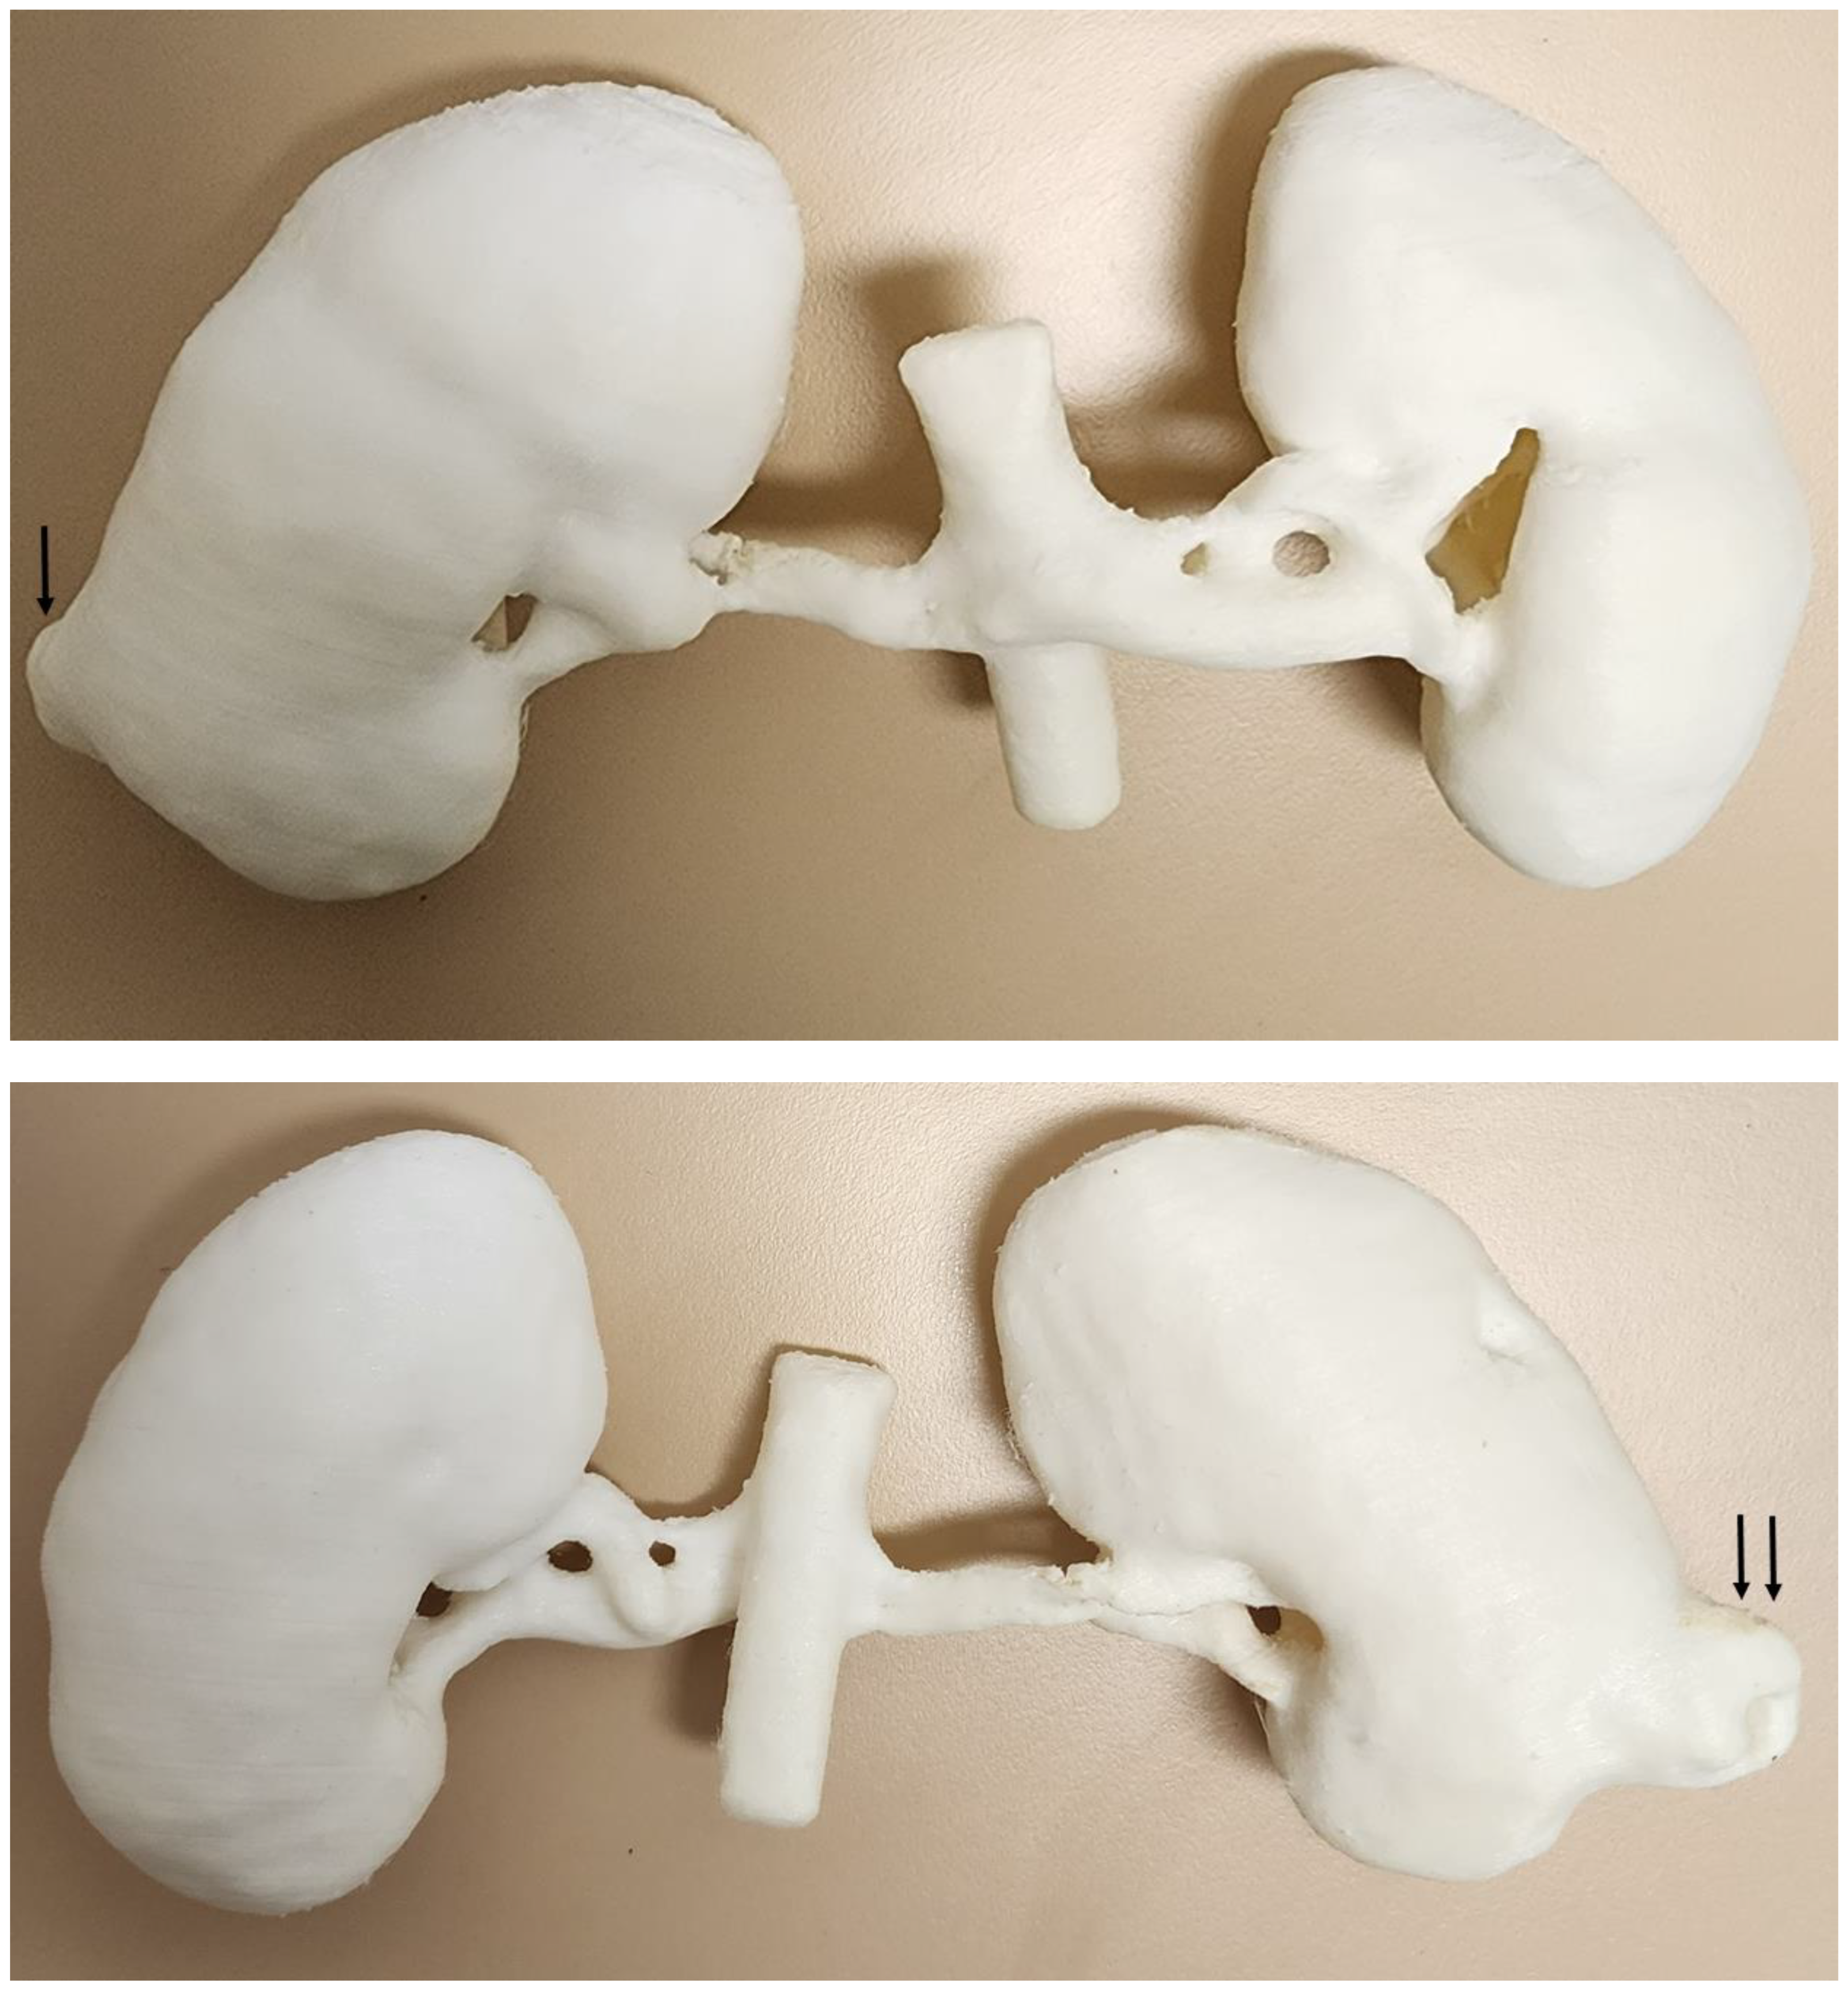

5.4. 3D-Printed Pancreatic Cancer Model

| Kidneys | 1 | CT | Renal cell carcinoma for preoperative planning | Ultimaker 2+ Extended Material: TPU 95A Cost: USD 20 | Model was printed at a resolution of 12.5 μm for the x, y and z-axis planes Time: ~70 h |